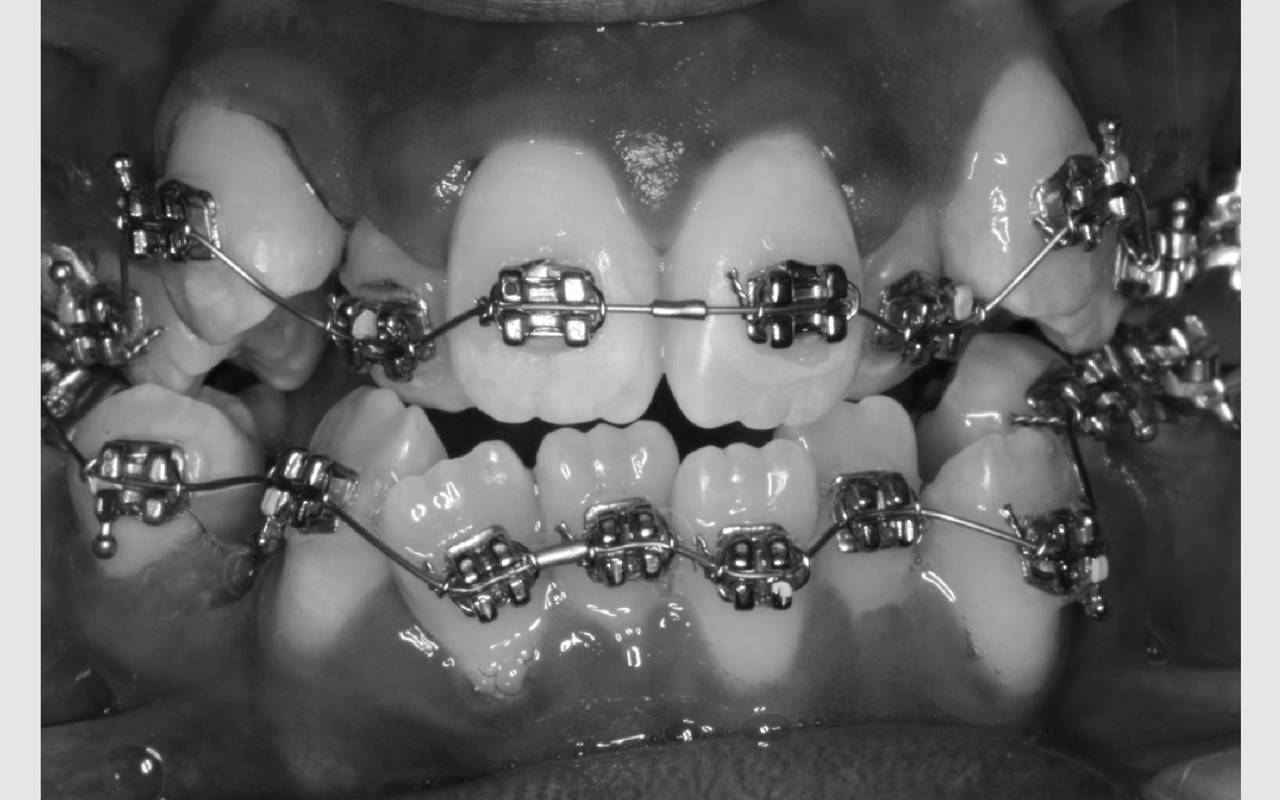

Faste bøjler - "togskinner"

Ofte er der brug for fastsiddende bøjler på tænderne. Mange kalder dem "togskinner", hvilket er et passende navn, da tænderne nærmest bliver flyttet i et spor på den lås, der limes på tanden.

Kontrol af din bøjle foregår på Tandreguleringsklinikken cirka hver 6. uge. Det varierer lidt gennem behandlingen afhængig af, hvilken fase, du er i. Ofte bliver du bedt om at bruge nogle elastikker mellem bestemte tænder. Det er yderst vigtigt, at du følger det, der aftales fra gang til gang, så behandlingen går hurtigst og bedst.

Når du har bøjle på, er det vigtigt, at du spiser med omtanke. Risikoen for huller i tænderne er langt større, når du har bøjle på. Du bør derfor spise sundt og undgå for meget sukker. Hold dig desuden fra hårde og seje ting, der kan beskadige bøjlen.

Får du bidt en lås af eller deformeret buen, er det vigtigt, at du ringer til Tandreguleringsklinikken og får en ekstra tid, så bøjlen kan blive repareret. Bøjlen skal hele tiden være i orden for at fungere optimalt.